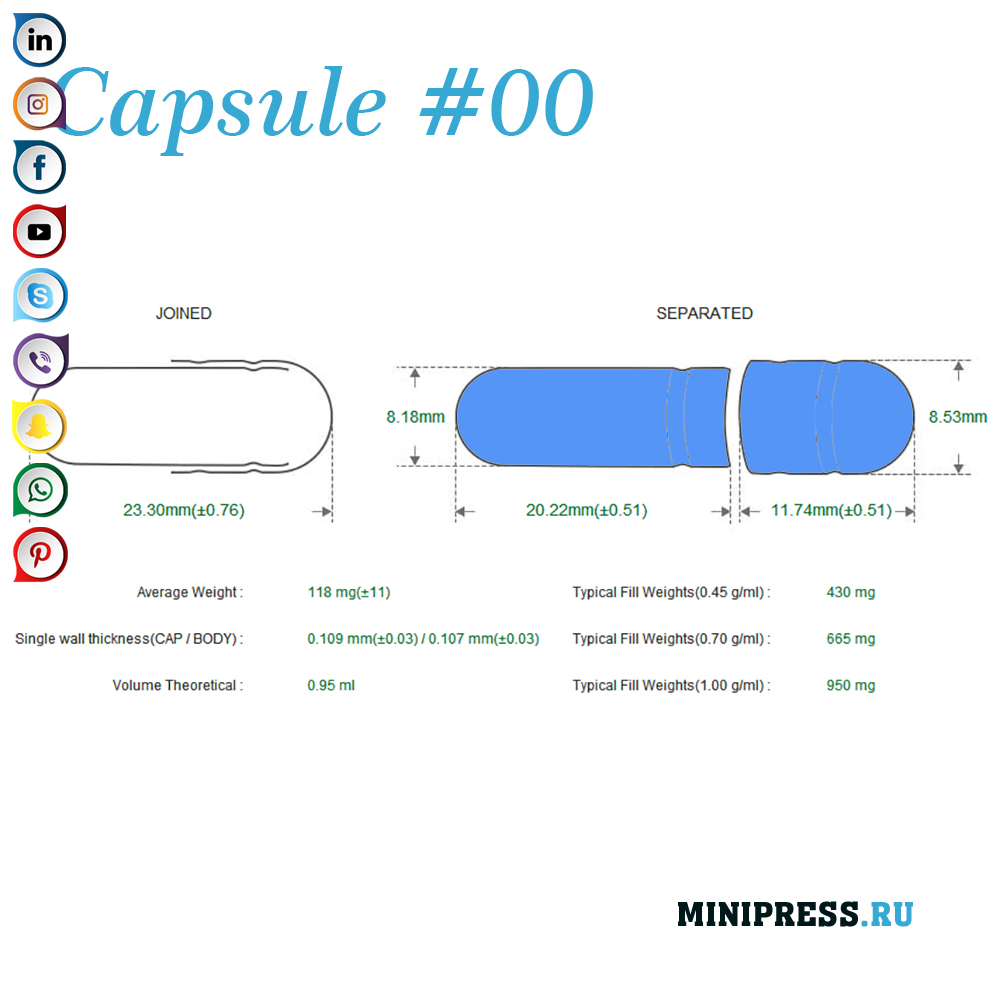

Velike zelatinskih kapsula: 000,00,0,1,2,3,4,5, A, B, C, D, E.